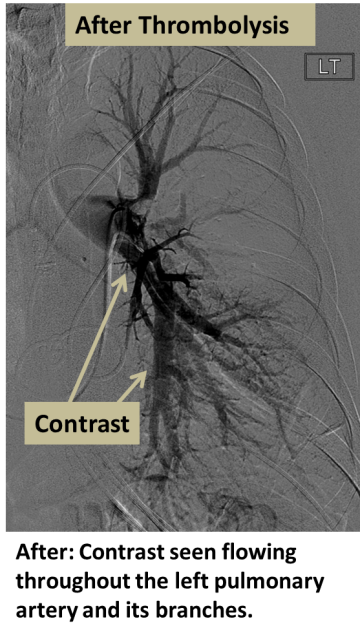

After: Contrast seen flowing throughout the left pulmonary artery and its branches